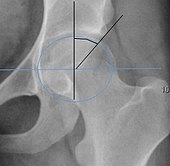

3. Impingement: Hip impingement, also known as femoroacetabular impingement (FAI), occurs when there is abnormal contact between the ball and socket of the hip joint. This can cause clicking, especially during movements that involve deep hip flexion.

Hip flexor Muscles 2. Labral Tear 3. Impingement 4. Muscles around the hip

Images courtesy of: 1. www.kenhub.com 2. https://commons.wikimedia.org/wiki/File:Labral_tear_2.svg 3.https://en.wikipedia.org/wiki/Femoroacetabular_impingement 4. https://commons.wikimedia.org/wiki/File:Anterior_Hip_Muscles_2.PNG